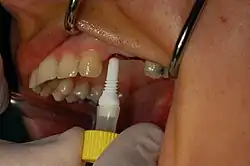

Установка зубных имплантатов может вести к периимплантиту, который возникает из-за бактериальной флоры, попадающей на внешнюю поверхность имплантатов через зубной налет. Лечение данного заболевания проводили корейские исследователи с использованием титановой щетки.

- исследуется состояние зубов;

- выполняется профессиональная чистка зубов и имплантатов от зубного камня. Гигиена является важнейшим фактором долгого срока службы зубных имплантатов.